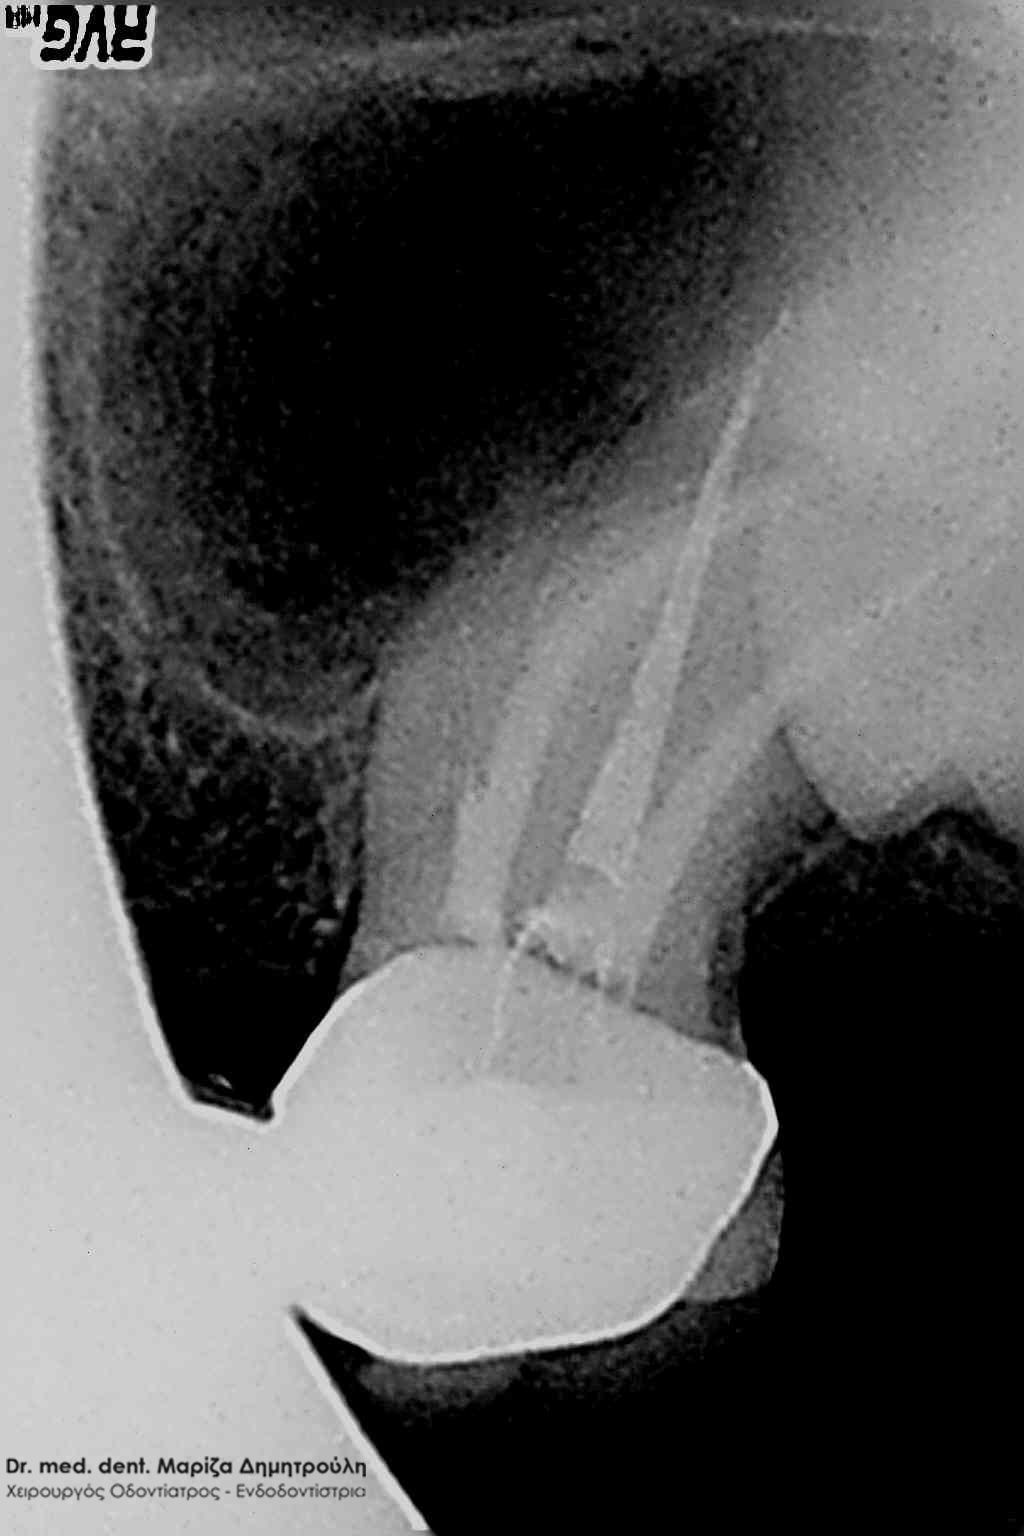

Διαπίστωση της διάτρησης

Εντοπισμός του τρίτου ριζικού σωλήνα

Ολοκληρωμένη απονεύρωση

Η ασθενής απευθύνθηκε στο ιατρείο γιατί το συγκεκριμένο δόντι έδινε συμπτώματα πόνου παρόλο που είχε ξεκινήσει η διαδικασία της απονεύρωσης. Μετά την κλινική εξέταση του δοντιού διαπιστώθηκε διάτρηση μεταξύ των ριζικών σωλήνων του δοντιού, η οποία επιβεβαιώθηκε με τη λήψη ακτινογραφίας (πρώτη ακτινογραφία). Το σημείο της διάτρησης εμφράχθηκε με ειδικό υλικό. Στη συνέχεια εντοπίστηκε ο τρίτος ριζικός σωλήνας, ο οποίος δεν είχε βρεθεί ως εκείνη τη στιγμή (δεύτερη ακτινογραφία). Στην επόμενη συνεδρία οι ριζικοί σωλήνες του δοντιού καθαρίστηκαν με μηχανοκίνητα εργαλεία, απολυμάνθηκαν και εμφράχτηκαν με γουταπέρκα. Ακολούθησε η αποκατάσταση του δοντιού.